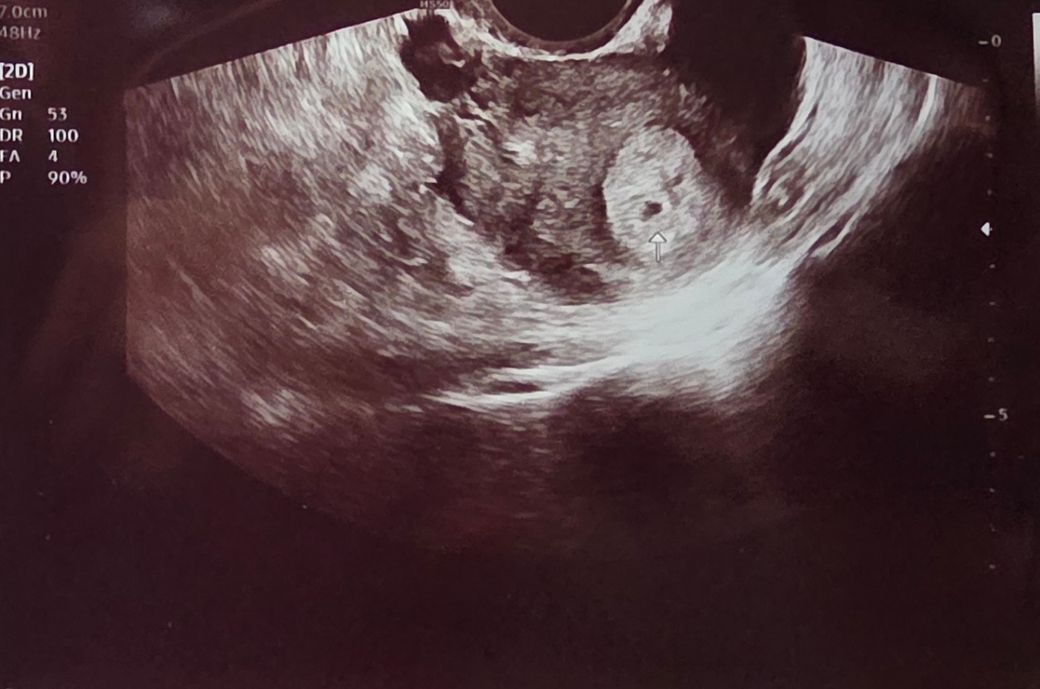

초음파 사진 쌍둥이 일수도 있나요?궁금해요!

산부인과 가서 초음파 받았는데

아직 초기라서 임신 진단 확인서는 못받았는데요.

일주일 뒤에 오면 아기집이랑 확실히 볼 수 있다고 그랬는데, 그 때 가면 가능할까요?

그리고 주위 사람들한테 사진 보여주니 화살표 오른쪽 위에 검은 점 한개가 보인다고 쌍둥이 아니냐는데

쌍둥이 일 수 도 있나요?

현재로서는 두 개의 아기집이 명확하게 관찰되지 않습니다.

시간이 어느정도 더 흐른 후에 초음파 검사를 확인하는 것이 정확하겠습니다.

지금 당장 초음파 사진으로는 다태아보다는 단태아의 가능성이 높아 보입니다.